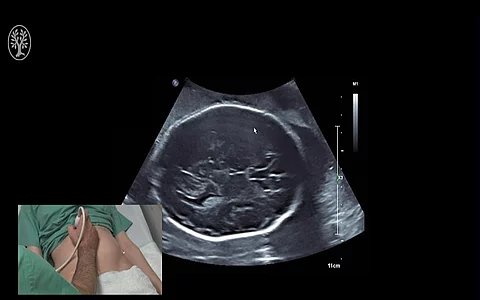

Nehmen Schwangere die Bewegungen ihres Kindes im Mutterleib weniger wahr, wird dies nicht immer ernstgenommen und überprüft. Dabei ist das Risiko für schwere Komplikationen hoch und eine schnelle Abklärung notwendig.

Für Sie operierte PD Dr. Markus Hoopmann aus dem Department für Frauengesundheit Tübingen. Es moderierten: Prof. Dr. Bernhard Krämer und OA Dr. Felix Neis.